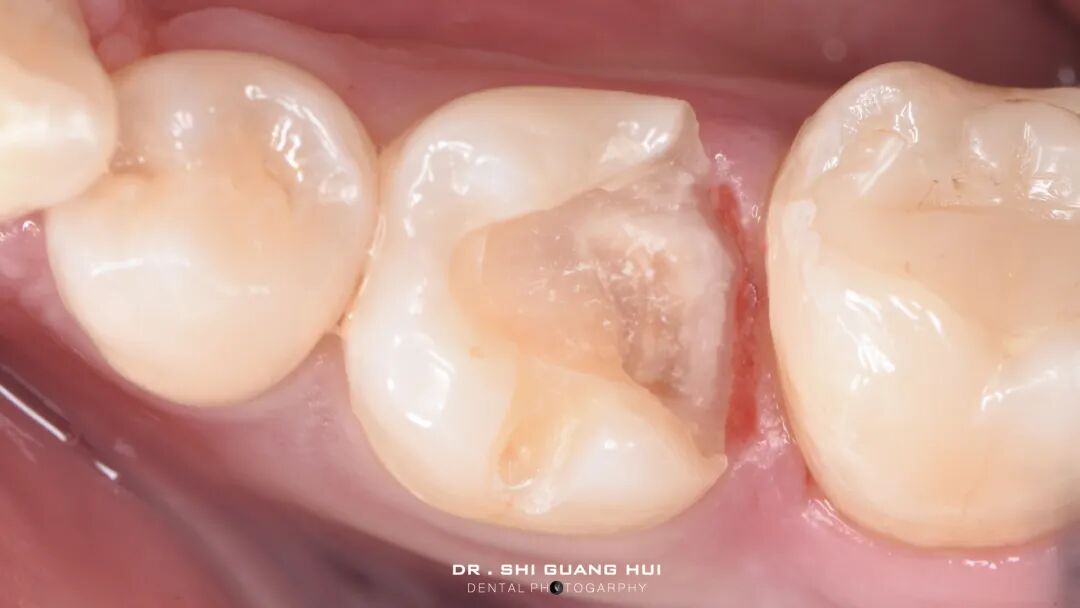

局部麻醉下进行去除腐质,可见远中邻面边缘位于龈下。由于近髓,剩余核心区域腐质橡皮障隔离后再进行去除。

橡皮障隔离患牙,去净腐质,然后进行详细的生物力学分析,远中舌尖无牙本质支撑,需要牙尖覆盖,降低1.5mm左右,远中颊尖厚度足够。近中邻面边缘嵴完整,远中邻面边缘需要进行CMR。

圈型成型片完美隔离,喷砂牙本质表面,将牙本质表面进行37%磷酸酸蚀15秒,轻轻风干5秒后涂布粘接系统,进行IDS。

进行IDS,远中邻面进行CMR

进行牙体预备,抛光牙面,保持内线角圆钝,检查功能尖和洞缘的距离。